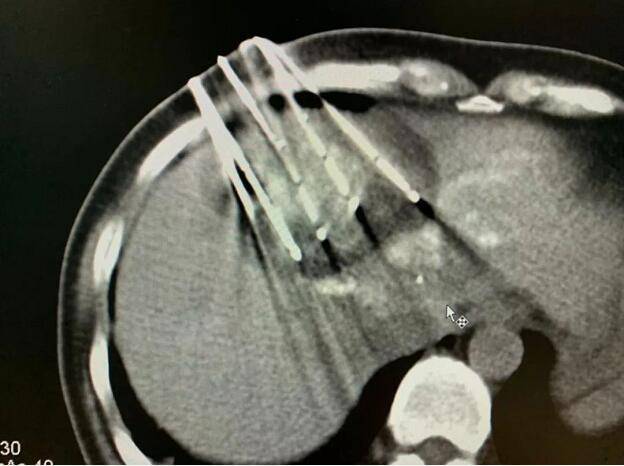

因为肝上的肿瘤比较大 , 血运很丰富 , 所以 , 复大的专家团队首先为她做了介入栓塞治疗 。 然后第二步 , 为她做了冷冻消融 。 接着 , 在椎体上的肿瘤做了冷冻加粒子植入 。

文章图片

做完治疗两周以后 , 再复查CT , 肿瘤基本上都坏死了 。 作为一名影像学专家 , 苏女士自己看了片子以后 , 对自己的治疗效果非常满意 。